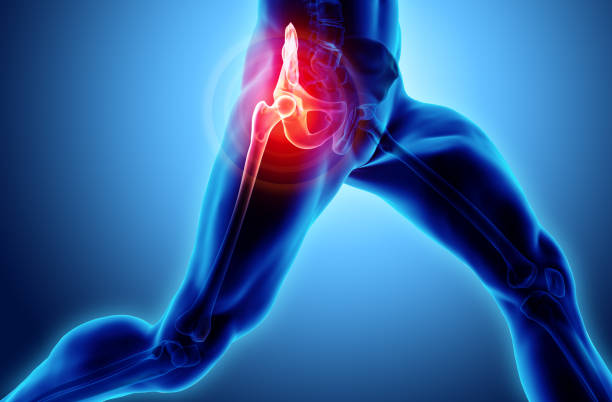

고관절 수술 후 회복에 필요한 시간을 알려드려요. 고관절 수술은 고관절의 변화로 인한 통증 및 기능 장애를 개선하기 위해 수술적인 처리를 하고, 수술 후 환자들은 회복 기간을 거치게 됩니다.

이 글에서는 고관절 수술 후 회복 기간과 주의사항에 대해 알려드리도록 하겠습니다.

고관절 수술후 회복기간- 수술 후 1주일: 치료와 통증 관리

수술 후 1주일은 가장 중요한 시기입니다. 이 때에는 처음 수술에 대한 통증이 가장 심하며, 치료와 통증 관리에 집중해야 합니다. 수술 부위를 올바르게 관리하고, 의사의 지시에 따라 정확히 약물을 복용하는 것이 중요합니다. 또한, 특별한 동작을 하지 않도록 주의해야 합니다. 1주일 동안은 휠체어를 사용하거나 보조기를 사용하는 것이 좋습니다.